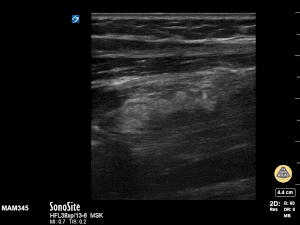

11y female with L both bone forearm fx from fall during gym class. Long axis view with clear discontinuity of proximal and distal components of the shaft. Transverse view with transition from single bony cortex to overlap of fracture ends. Matthew Moake, MD PhD